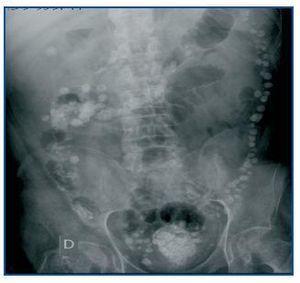

El carbonato de lantano es un quelante del fósforo, libre de calcio y aluminio, de reciente comercialización en España. Se trata de un metal pesado con nula absorción intestinal que no presenta toxicidad. En la ficha técnica del producto en nuestro país, no se cita el fenómeno de aparición de imágenes radiológicas. No ocurre así en la versión americana, donde se advierte que «pueden aparecer imágenes radioopacas en la radiografía abdominal en pacientes consumidores de lantano»1. Las reacciones adversas notificadas con mayor frecuencia fueron gastrointestinales, pero en los ensayos clínicos no se incluyeron pacientes con obstrucción intestinal ni enfermedad inflamatoria intestinal2. Presentamos el caso de un hombre de 58 años, con diverticulosis pancolónica y frecuentes episodios de diverticulitis, con ERC secundaria a nefropatía diabética e inicio de programa de hemodiálisis periódica en abril de 2001. Ingresa en julio de 2008 por fiebre y dolor abdominal. Se realiza una TAC abdominal urgente que descarta signos de diverticulitis, pero es informado por el radiólogo como «restos de contraste en todo el colon e íleon terminal» (figura 1), imagen confirmada en una radiografía simple de abdomen (figura 2). Nuestro paciente no había recibido contraste radiológico en ningún momento, pero estaba siendo tratado con 3.000 mg diarios de carbonato de lantano desde febrero de este año por hiperfosforemia grave, con excelentes resultados analíticos y buena tolerancia clínica hasta el momento. El diagnóstico final fue de sepsis por Enterococo avium, de probable origen intestinal. Dado que no se encontraron otros hallazgos en las pruebas de imagen que justificaran el dolor abdominal, se suspendió el tratamiento con lantano, permaneciendo posteriormente asintomático.

Figura 2. Radiografía simple de abdomen sin contraste que muestra múltiples opacidades centriméticas de distribución irregular en la periferia del marco cólico, que reflejan depósito de lantano en los divertículos.